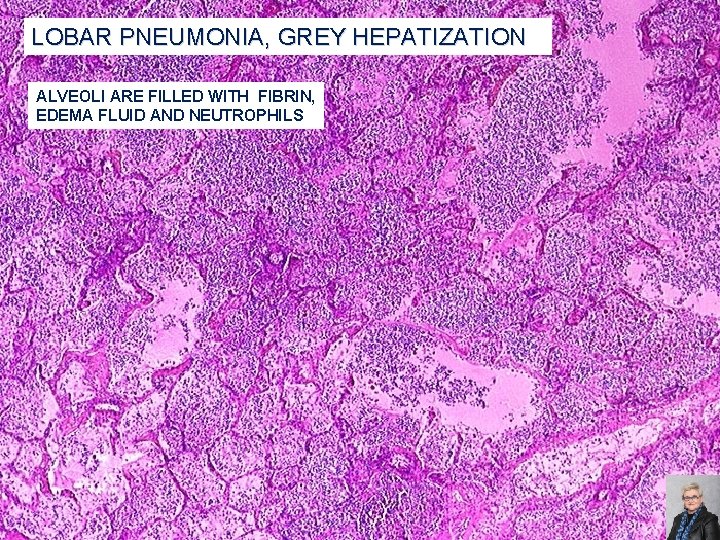

LOBAR PNEUMONIA; CLASSIC STAGES (AS SEEN IN PNEUMOCOCCAL PNEUMONIA) Congestion: �Heavy, boggy, red, hyperemic lungs with many bacteria but few neutrophils Red hepatization: �Massive confluent alveolar filling with RBCs, neutrophils, and fibrin Gray hepatization: �Disintegrating RBCs and fibrinopurulent exudate fill alveoli Resolution: �Macrophages mop up debris and normal function returns 59

LOBAR PNEUMONIA, GREY HEPATIZATION ALVEOLI ARE FILLED WITH FIBRIN, EDEMA FLUID AND NEUTROPHILS 64

LOBAR PNEUMONIA, GREY HEPATIZATION -HYPEREMIA -EXUDATE WITH FIBRIN STRANDS AND PMNs FILLS ALVEOLI -SIDEROPHAGES: IRON-CONTAINING MACROPHAGES 65